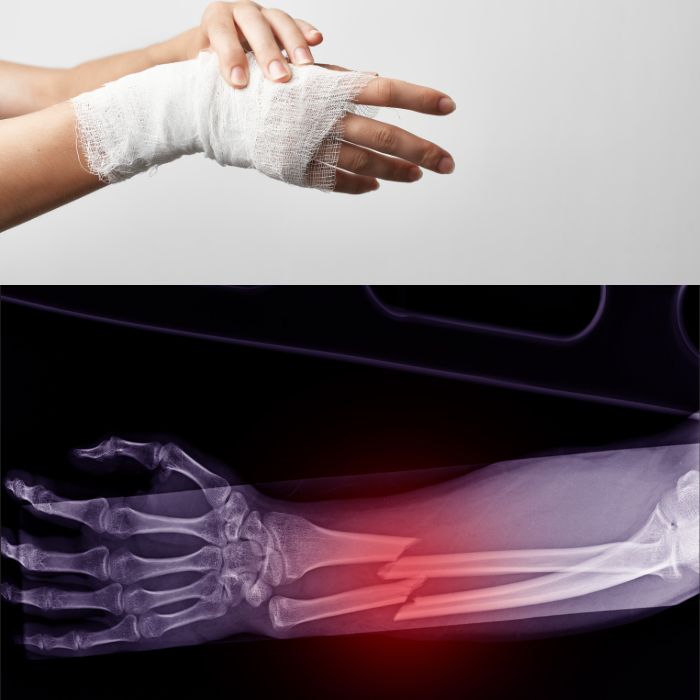

엄마가 넘어지며 팔목골절로 철심을 넣는 수술을 하셨어요. 오른손을 다치셔서 생황이 불편하시니 음식이라도 챙겨드리고싶은 마음인데요. 이왕이면 골절후 뼈건강 회복에 좋은 음식이 궁금해졌어요.

나이가 들면 뼈가 약해지고 골절 위험이 커져요. 특히 골다공증이 있는 경우 작은 충격에도 쉽게 골절될 수 있죠. 뼈가 부러지면 회복하는 데 시간이 오래 걸리고, 생활의 질도 크게 떨어질 수 있어요. 하지만 적절한 영양 섭취를 하면 회복을 빠르게 도울 수 있답니다.